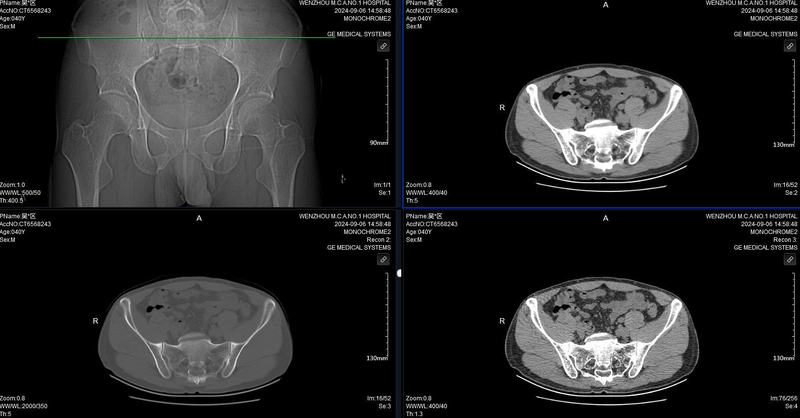

病例?患者,男,40歲。雙側(cè)屁股肉疼痛有3年,一開(kāi)始右單側(cè)肌肉痛,偶發(fā)性疼,后左側(cè)偶爾疼。?MRI:雙側(cè)骶髂關(guān)節(jié)炎性改變。討論?在人體的骨骼結(jié)構(gòu)中,骶髂關(guān)節(jié)扮演著至關(guān)重要的角色。然而,當(dāng)雙側(cè)骶髂關(guān)節(jié)出現(xiàn)炎癥時(shí),會(huì)給患者帶來(lái)諸多不適和困擾。?雙側(cè)骶髂關(guān)節(jié)炎是一種常見(jiàn)但常被忽視的疾病,了解其癥狀及相應(yīng)的對(duì)策對(duì)于患者的康復(fù)至關(guān)重要。?雙側(cè)骶髂關(guān)節(jié)炎的癥狀多種多樣,且具有一定的隱匿性。早期癥狀可能較為輕微,患者可能會(huì)感到下腰部或臀部的隱隱作痛,這種疼痛通常在活動(dòng)后加重,休息后有所緩解。?隨著病情的進(jìn)展,疼痛會(huì)逐漸加劇并變得持續(xù),甚至可能放射至大腿后側(cè)、腹股溝及小腿部位。?患者在行走、站立或久坐后起身時(shí),會(huì)感到明顯的困難和疼痛,嚴(yán)重影響日常生活的質(zhì)量。?除了疼痛,關(guān)節(jié)的僵硬感也是雙側(cè)骶髂關(guān)節(jié)炎的常見(jiàn)癥狀之一。尤其是在早晨起床時(shí),患者會(huì)感覺(jué)腰骶部僵硬,活動(dòng)受限,需要經(jīng)過(guò)一段時(shí)間的活動(dòng)才能逐漸緩解。?部分患者還可能出現(xiàn)關(guān)節(jié)腫脹、發(fā)熱等癥狀,關(guān)節(jié)的活動(dòng)度也會(huì)逐漸減小,導(dǎo)致彎腰、轉(zhuǎn)身等動(dòng)作變得不再靈活。?面對(duì)雙側(cè)骶髂關(guān)節(jié)炎,我們并非束手無(wú)策。首先,明確診斷是關(guān)鍵。醫(yī)生通常會(huì)通過(guò)詳細(xì)的病史詢問(wèn)、體格檢查、影像學(xué)檢查(如X光、CT、磁共振成像等)以及實(shí)驗(yàn)室檢查(如血沉、C反應(yīng)蛋白等)來(lái)確診病情,并評(píng)估疾病的嚴(yán)重程度。治療?在治療方面,早期的保守治療往往能取得較好的效果。藥物治療:非甾體類抗炎藥如布洛芬、雙氯芬酸鈉等可以有效減輕疼痛和炎癥。對(duì)于病情較重或藥物治療效果不佳的患者,可能需要使用免疫抑制劑或生物制劑來(lái)控制病情的進(jìn)展。物理治療:包括熱敷、冷敷、按摩、針灸、超聲波治療等,這些方法有助于緩解疼痛、放松肌肉、改善關(guān)節(jié)活動(dòng)度。病變嚴(yán)重時(shí)可以做射頻松解治療在治療肌筋膜炎時(shí),醫(yī)生會(huì)在影像學(xué)的引導(dǎo)下,將射頻針精準(zhǔn)地插入病變部位的肌肉筋膜組織。射頻電流產(chǎn)生的熱能能夠使病變組織中的膠原蛋白收縮、凝固,從而破壞疼痛感受器和神經(jīng)末梢,達(dá)到減輕疼痛、改善肌肉功能的目的。緩解疼痛、改善肌肉功能、促進(jìn)血液循環(huán)、軟化瘢痕組織。與傳統(tǒng)治療方法相比,射頻治療具有許多獨(dú)特的優(yōu)勢(shì)。首先,它具有較高的精準(zhǔn)性,能夠準(zhǔn)確地作用于病變部位,避免對(duì)周圍正常組織的損傷。其次,射頻治療的效果較為持久,能夠有效地緩解疼痛,減少?gòu)?fù)發(fā)的可能性。射頻治療的創(chuàng)傷較小,患者術(shù)后恢復(fù)較快,一般在治療后短時(shí)間內(nèi)即可恢復(fù)正?;顒?dòng)。患者自身的生活方式調(diào)整也起著至關(guān)重要的作用。保持良好的姿勢(shì),避免長(zhǎng)時(shí)間彎腰、久坐或久站,定期進(jìn)行適度的運(yùn)動(dòng),如游泳、瑜伽等,能夠增強(qiáng)腰背肌肉的力量,減輕關(guān)節(jié)的負(fù)擔(dān)。注意保暖,避免寒冷和潮濕的環(huán)境刺激,也有助于緩解癥狀。

王祥瑞醫(yī)生的科普號(hào)2024年09月09日580